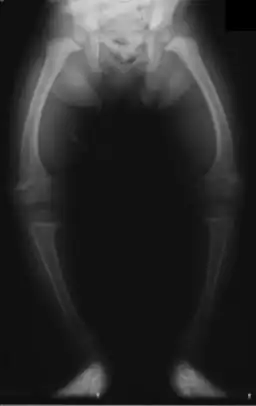

Kromme benen ten gevolge van rachitis | ||||

- verkromming van ledematen

- O-benen of X-benen